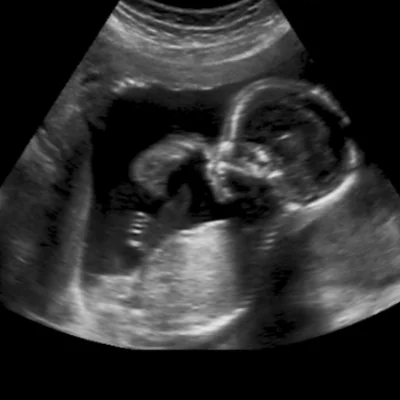

Obstetric Ultrasound

We specialize in obstetric imaging to support mothers and babies throughout pregnancy

Early Pregnancy Scans

Confirm gestational age and fetal viability

Fetal Growth Scans

Track development and detect anomalies

NT Scan

Nuchal translucency screening for chromosomal risks

Level II / TIFFA Scan

Detailed anomaly scan to assess fetal organs and structure

Our team ensures a calm, respectful environment for expectant mothers, with clear communication and compassionate care at every stage.